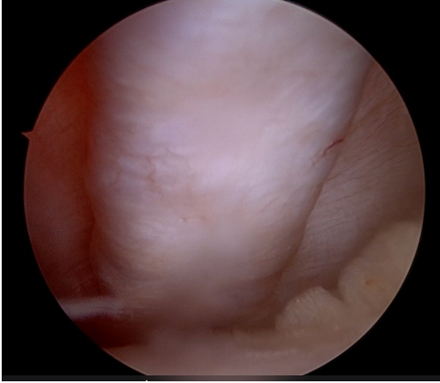

A high anterolateral arthroscopic portal was created for good visualization of the knee joint, and an anteromedial portal was created for instrumentation. A diagnostic arthroscopy was performed. The anterior cruciate and posterior cruciate ligaments were intact and taut. The patient had intact menisci along with healthy cartilage. An osteochondral fragment of the size of 2 cm × 2.5 cm was visualized floating in the joint. This fragment was identified from the posterolateral aspect of the LFC. The patellar facets and ridge were identified and were unremarkable. There were no other positive findings on the diagnostic arthroscopy. The fragment was removed from the anterolateral portal by increasing the incision to a length of 1.5 cm. Fig. 6.

A 2 cm incision was made over the anteromedial aspect of the tibia over the Pes insertion, and the semitendinosus and gracilis tendons were harvested, and the graft was prepared on the back table with a final length of 18 cm. A 4 cm long incision was made on the medial aspect of the femur, and the adductor tubercle was identified. The Schöttles point was identified using fluoroscopy guidance as the anatomic insertion point of the MPFL ligament. A guide wire was placed at this point, and serial reaming was done over this guide wire with a 6 mm drill bit in the anterior and superior direction. A 2 cm long incision was made on the medial aspect of the patella, and dissection was done to identify the medial ridge of the patella. A drill guide for the suture anchors was used to create 2 tunnels to receive the suture anchors on the medial aspect of the patella. These drill holes were drilled under arthroscopic guidance to make sure the drills do not enter the joint and stay extra-articular. 2 × 4 mm double-loaded suture anchors were inserted into the patella drill holes. A tunnel was created inside layer 2 of the medial patello-femoral tissue complex, and the graft was tunneled through this tissue tunnel with the combined limb, along with the femoral fixation endobutton kept at the mouth of the drilled femoral hole and the U-limb of the graft kept near the patella. The graft was locked into place with the double-loaded suture anchors and was tightened securely with locking knots. A thread was passed through the femoral tunnel, and the endobutton was pulled through the tunnel and flipped on the lateral aspect of the distal femur. The graft was tightened in place by pulling on the tensioning threads after flexing the knee to 30° flexion. The position of the patella and tension on the MPFL graft were monitored during the tightening of the graft and were satisfactory post-tightening. Appropriate care was taken to avoid over-tensioning the MPFL and making sure Grade 1 patella glide was present after tightening. A fluoroscopy shot was taken to confirm the position of the endobutton on the cortex of the lateral femur. The knee was flexed to 60° and a 5 cm skin incision was taken along the lateral aspect of the patella, and a lateral parapatellar arthrotomy was performed. An arthroscopic burr was used to freshen the bed of the osteochondral fragment base on the femoral condyle base till fresh bleeding was visualized. The previously removed osteochondral fragment was placed in position under direct vision and was temporarily fixed in a reduced position with two guide pins for headless screws. Two bioabsorbable PLLA pins of diameter 2.7 mm were used to stabilize the fragment after predrilling with the provided drill. The two headless screw guide pins were over-drilled with the help of the drill bit, and two headless screws of length were introduced and fixed. The stability of the fragment was assessed by moving the knee through its range of movement. Fig. 7,8.

Figure 7: Osteochondral defect of lateral femoral condyle.

Figure 8: Lateral femoral condyle post fixation of defect.